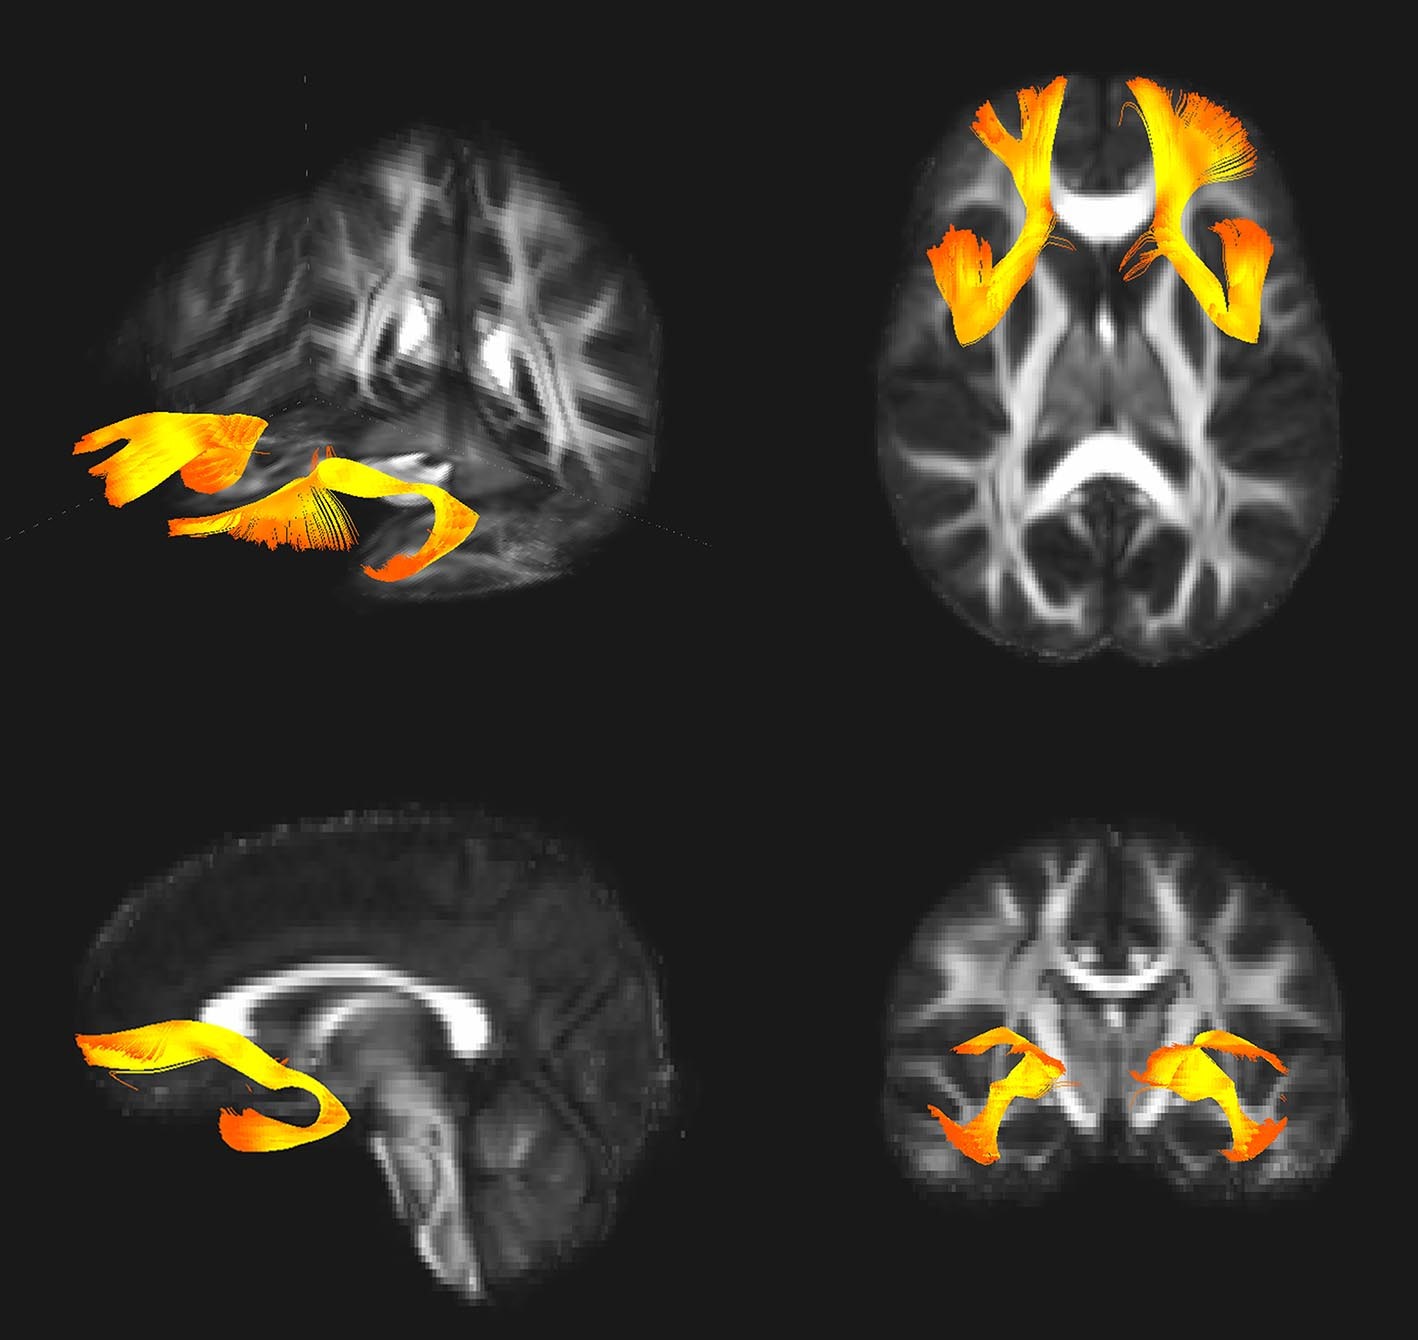

Connexions fronto-limbiques associé à la variation de SNAP25 visualisé en tractographie par IRM de diffusion

Les résultats révèlent que la variation du gène SNAP25 change l’expression de la protéine associée dans le cerveau, ce qui impacterait le traitement de l’information entre les régions cérébrales impliquées dans la régulation des émotions. En lien avec ce mécanisme, l’étude d’imagerie génétique, combinant IRM anatomique et fonctionnelle de repos, montre que dans les deux cohortes, le variant à risque est associé à un plus grand volume d’une zone cérébrale, l’amygdale, et une connectivité fonctionnelle préfronto-limbique altérée.

Photo : Réseau préfronto-amygdalien associé à la variation de SNAP25 visualisé en tractographie par IRM de diffusion. Crédit: Josselin Houenou /BrainVisa/Connectomist 2.0